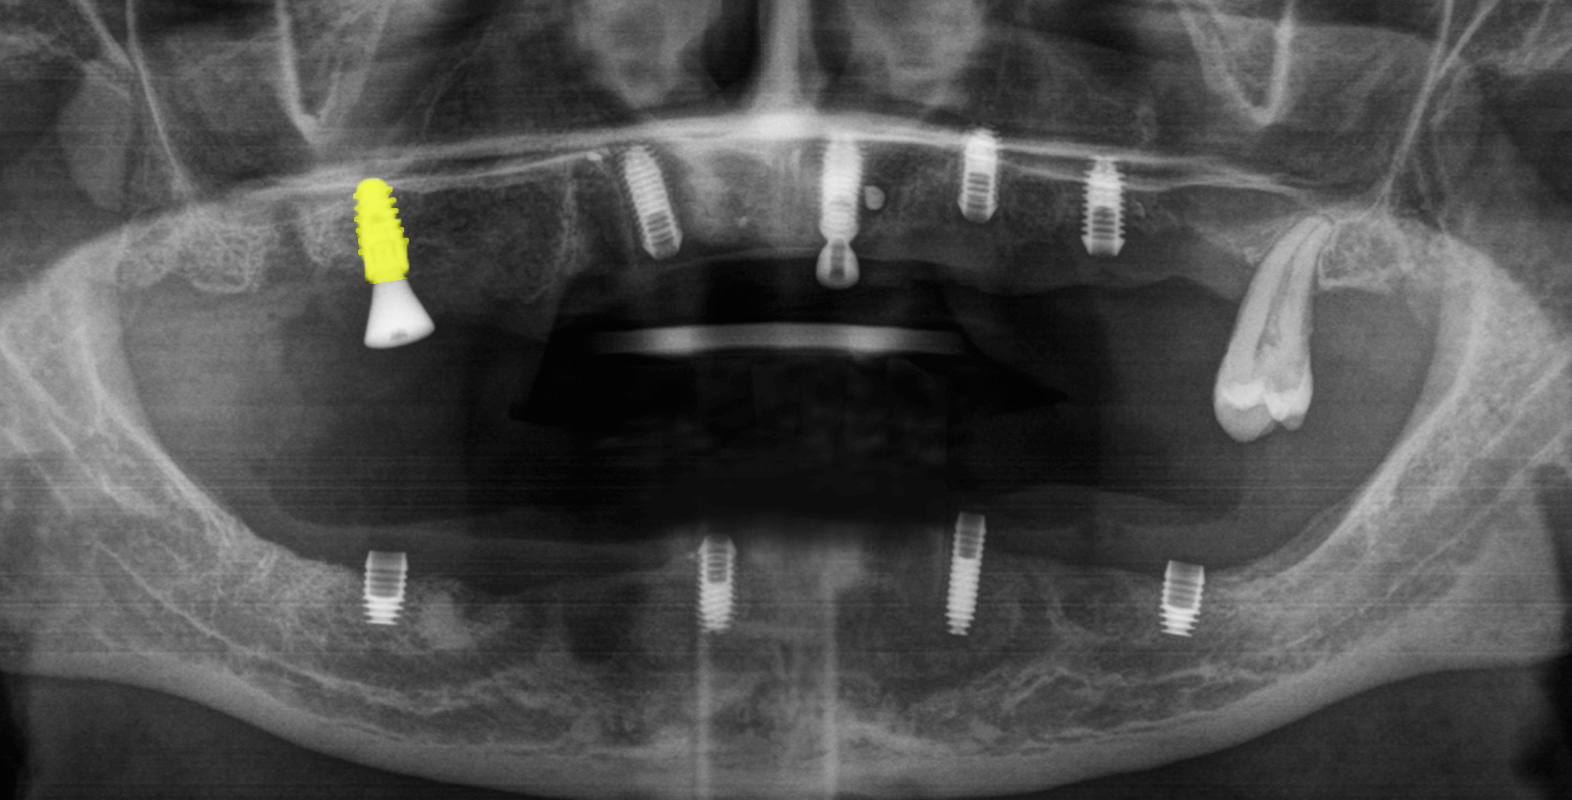

Согласно данным на снимке импланты были расположены не в одной плоскости (нарушена параллельность) и это могло вызвать сложность при протезировании цельнолитой конструкцией, однако при слаженной работе врача и зубного техника был шанс получить положительный результат.

- Добавить 1 зубной имплант Straumann в области зуба 1.6